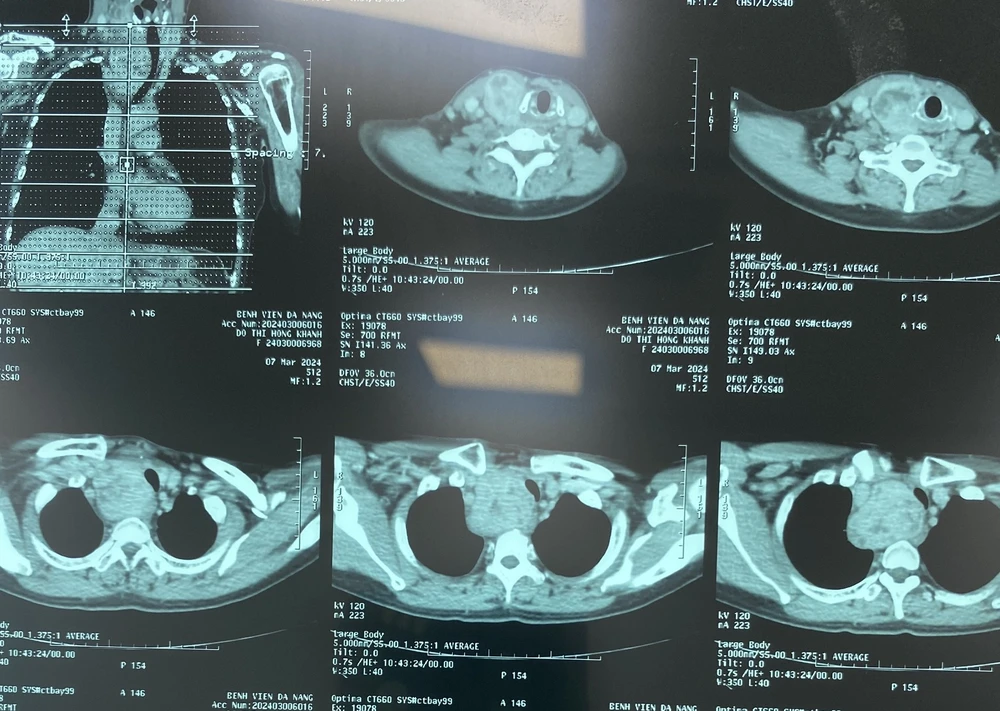

Qua thăm khám, bác sĩ phát hiện có khối u ở thùy phải tuyến giáp. Trên phim X-quang ngực có khối u vùng trung thất trên chèn ép khí quản ngực.

Khối bướu giáp thùy phải lớn thòng xuống trung thất, kích thước 5x15 cm, phần dưới khối u nằm ở vùng trung thất sau chạm đến động mạch chủ của bệnh nhân, khối u đẩy xẹp 50% khẩu kính khí quản ngực.